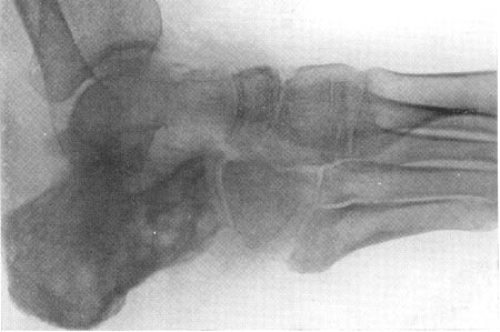

Повреждение протекает в сопровождении резкого остеопороза, в последующем в числе общего остеопороза на рентгенографических снимках выявляется в просветлении круглой формы, расположение соответствует месту распада остеоткани. В центральной части бесструктурного очага зачастую визуализируются типичные для туберкулеза секвестры с наличием изъеденных очертаний. Утончение коркового вещества и прорывание очага из костной структуры в суставную полость представлены воспалительным процессом в синовиальной мембране с наростом на ее плоскости гранулирований и выпячиванием их в полости артрсоединения. В последующем последние претерпевают казеозный некротический распад с деструкцией эпифизарного хондрального слоя и остеоткани, что рентгенологически визуализируется узурами эпифизарных границ и деструктивными трансформациями в артрконцах костей.

Отсутствие склеротической области в параочаговой зоне и периостального ответа выступает патогномоничной характеристикой туберкулезного воспаления кости (остита). В запущенных вариантах развиваются натечные абсцессы, свищевые ходы с гнойным отделимым, фибриновых хлопьев, «рисовых тел», в некоторых случаях тканевых частиц.